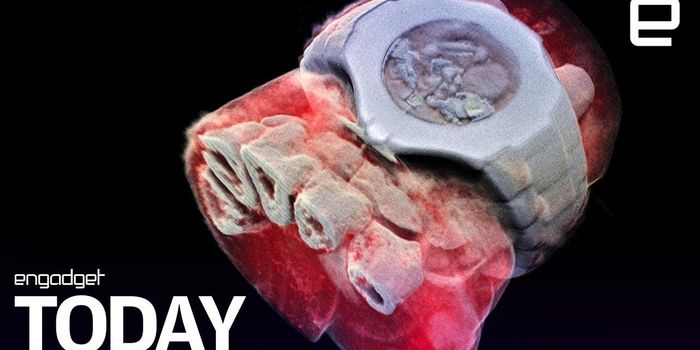

JUL 20, 2018Chemistry & PhysicsIn the near future, the X-ray images from your doctor's office will no longer be just black and white, at least that ...